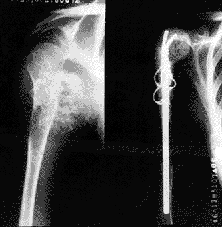

肱骨近端肿瘤切除后肩关节功能的重建

肱骨近端低度恶性肿瘤及一些反复复发的类肿瘤样病变行瘤段切除后需重建肩关节以恢复上肢功能 ......